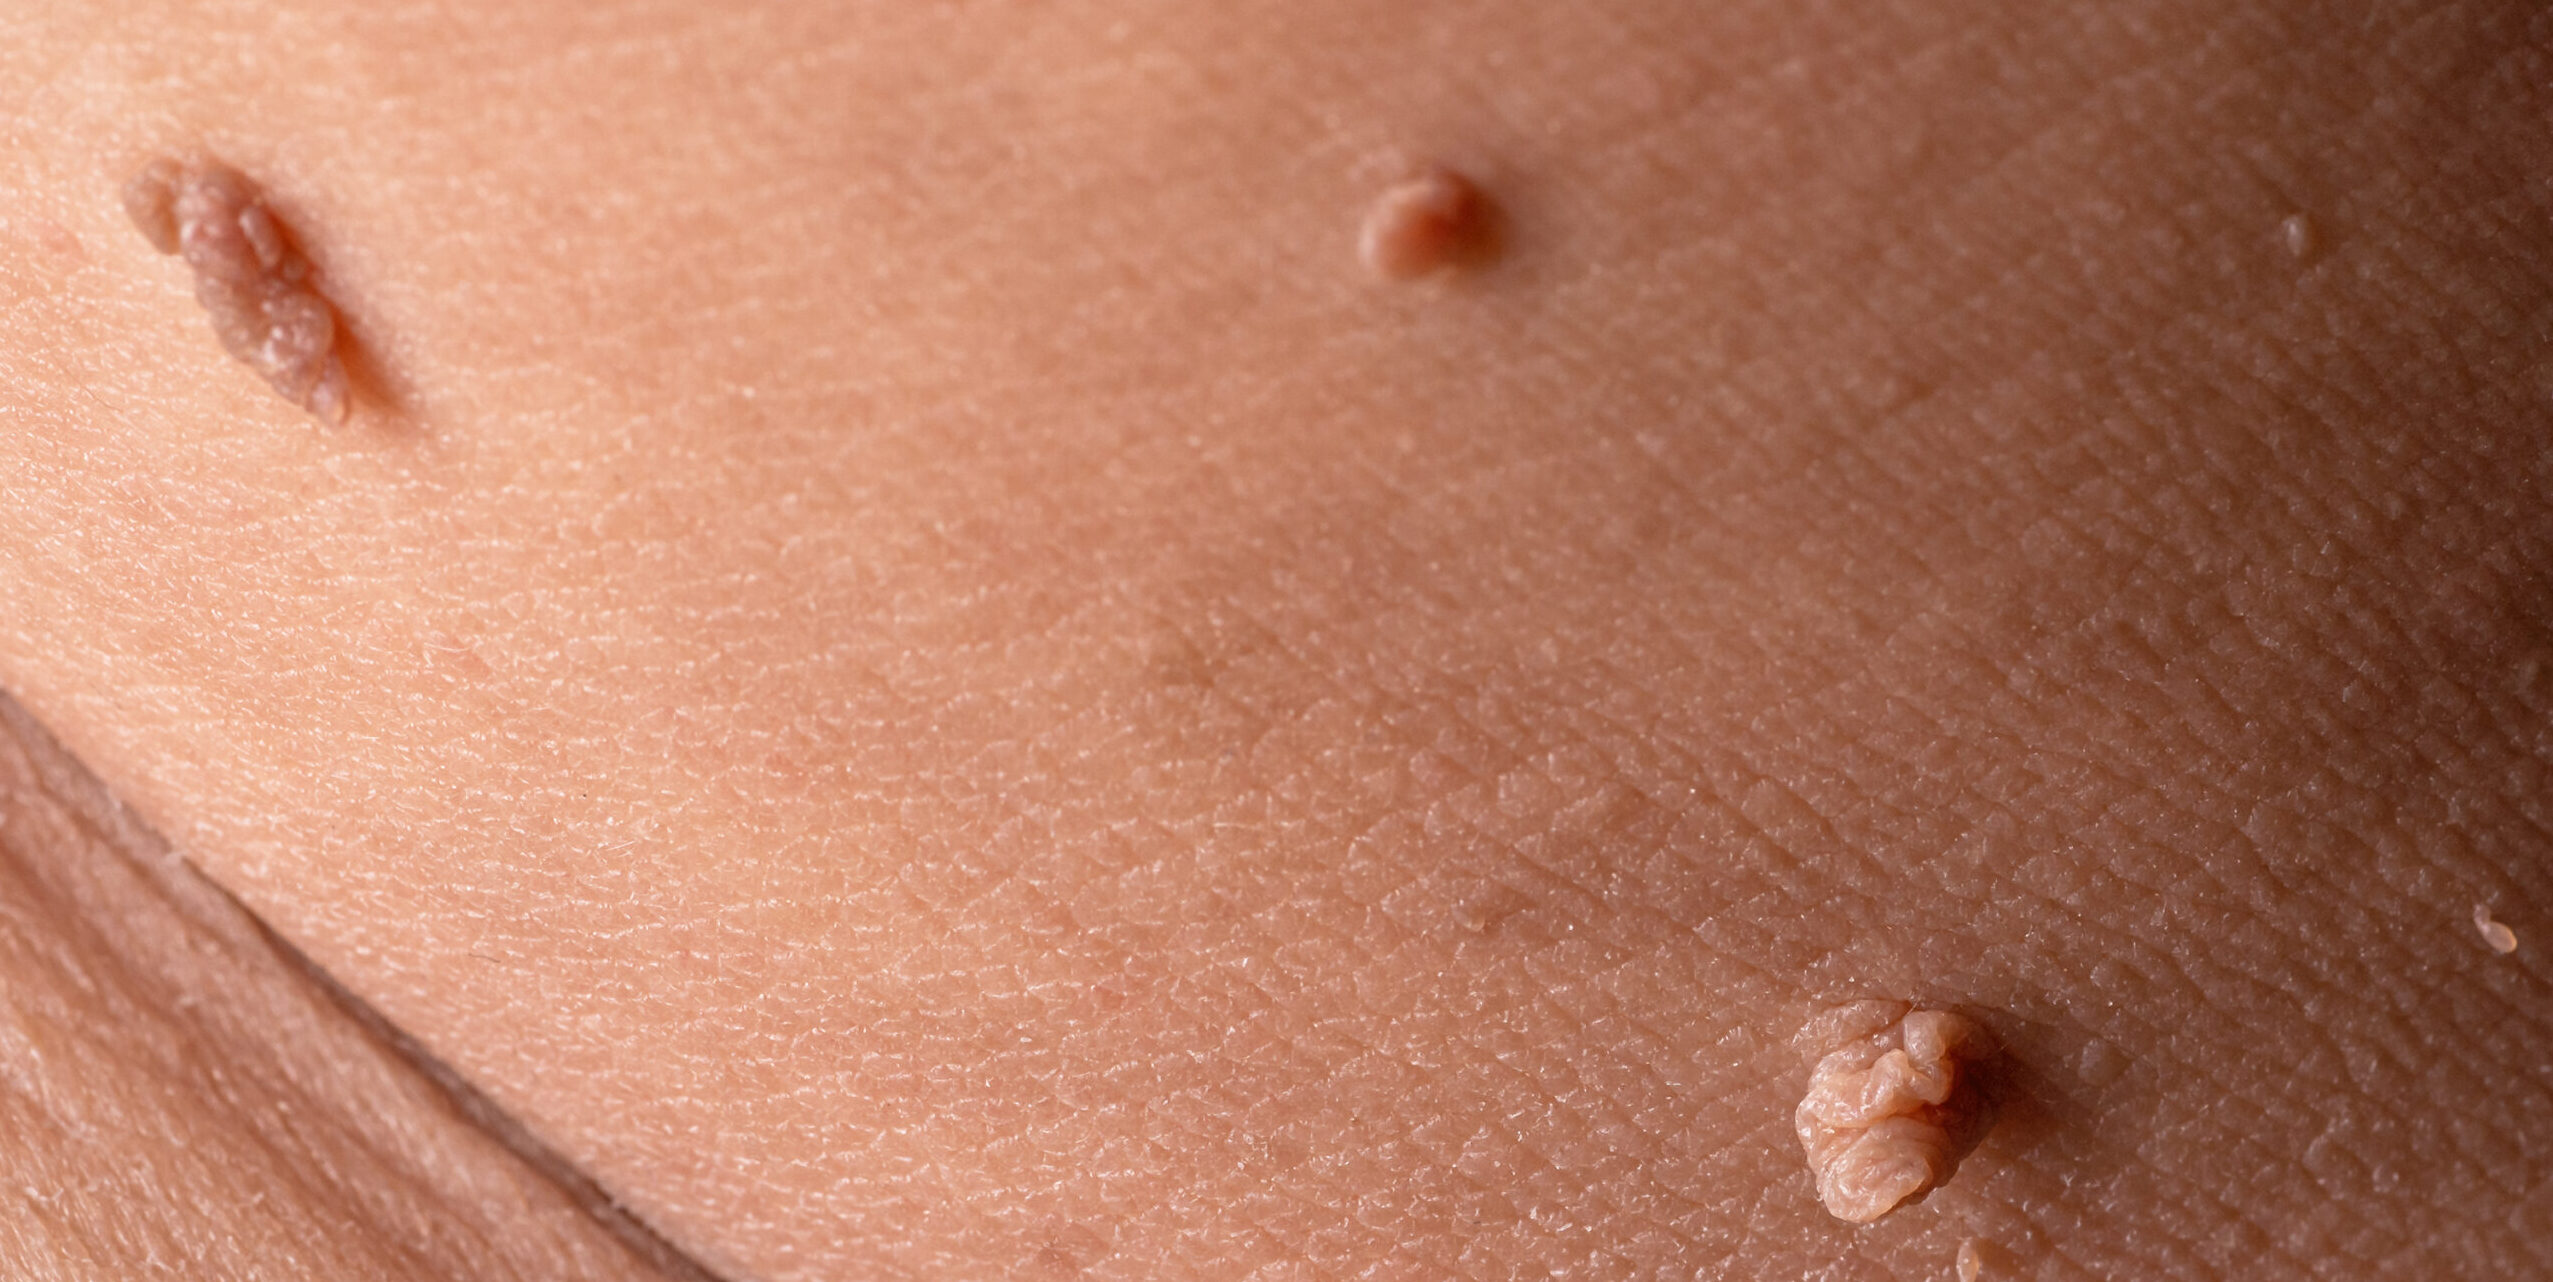

Labiaplasty, also known as labia minora reduction, is a surgical procedure that removes excess skin from the labia

There are various treatments that pertain to “vaginal rejuvenation” and labiaplasty one of them. Not one procedure is like the next, each one treats a certain case – with labiaplasty it specifically aims to decrease the size of the inner tissues of the female genitalia.

There are many reasons females have enlarged labia, such as:

– Childbirth

– Aging

– Sexual activity

– Genetics.

Many females with an enlarged labia have difficulty exercising, struggle with hygiene, urinary tract infections, sexual and other physical activities. Not to mention, that most women feel self-conscience about their appearance in tight clothes.